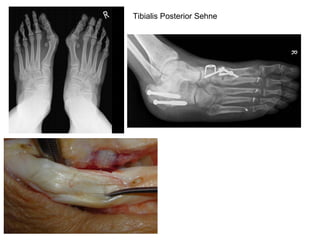

Tibialis Posterior   Sehne